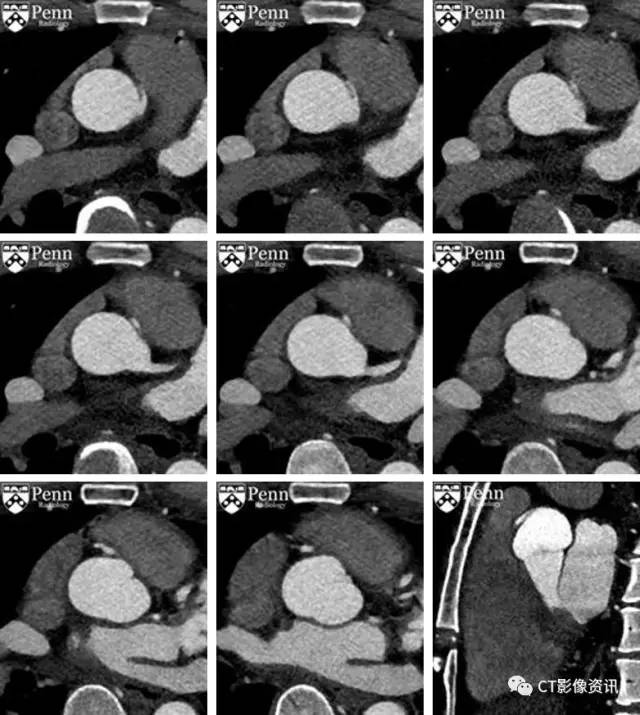

矢状位图像

影像学描述 右冠状动脉从左侧冠窦异常起源,右冠与冠窦之间夹角狭窄,开口呈狭缝状改变,在主动脉根部和近端肺动脉干之间走形(或者可能恰好邻近肺动脉瓣,示例图片可能显示的不好)。右冠状动脉近端主干的管径减小。未见冠状动脉钙化。